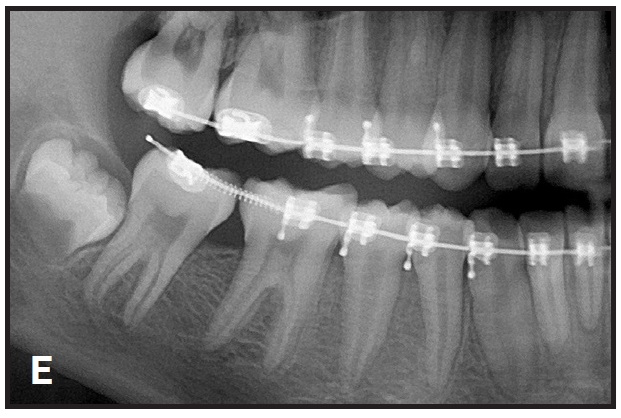

The second molar quickly uprights in one or two appointments (D). Note that a long cinch should always be placed at the end of the archwire (E).